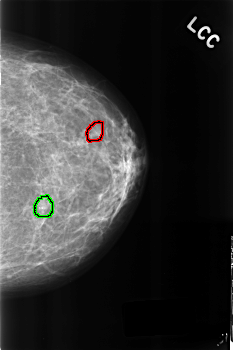

C_0271_1.LEFT_CC

LEFT_CC LINES 4544 PIXELS_PER_LINE 3024 BITS_PER_PIXEL 12 RESOLUTION 50 OVERLAY

FILE: C_0271_1.LEFT_CC.OVERLAY

TOTAL_ABNORMALITIES 2

ABNORMALITY 1

LESION_TYPE CALCIFICATION TYPE PUNCTATE DISTRIBUTION CLUSTERED

ASSESSMENT 4

SUBTLETY 5

PATHOLOGY BENIGN

TOTAL_OUTLINES 1

ABNORMALITY 2

ASSESSMENT 3

SUBTLETY 4